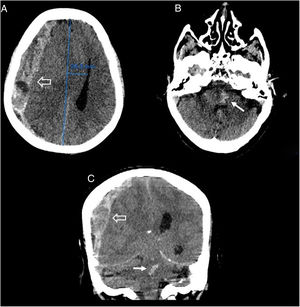

En la exploración clínica presenta un Glasgow de 4/15, presión arterial de 223/97mmHg, pH de 7,3 y un potasio de 6,3 mmol/l. Dado el rápido deterioro clínico, se solicita una tomografía computarizada (TC) craneal sin contraste por vía intravenosa (IV), visualizando un gran hematoma subdural agudo hemisférico derecho con signos severos de herniación subfalcina y transtentorial descendente (fig. 1A y C), focos hemorrágicos en mesencéfalo y protuberancia asociados (hemorragia de Duret), con extensión al acueducto de Silvio (fig. 1B y C).

Imágenes de TC craneal sin contraste intravenoso, cortes axiales (A y B) y coronal (C). Se identifica una colección hemorrágica extraaxial derecha de densidad mixta con morfología en semiluna en relación con un hematoma subdural agudo hemisférico derecho, de espesor máximo de 2cm (flecha hueca). Dicha colección ejerce marcados efectos expansivos condicionando una herniación subfalcina con desviación de la línea media hacia la izquierda de aproximadamente 25mm y colapso casi completo del sistema ventricular derecho, así como borramiento de las cisternas basales en relación con herniación transtentorial descendente, que asocia focos centrales hiperdensos en la protuberancia y el mesencéfalo, sugerentes de hemorragia de Duret (flecha fina), que se extiende al acueducto de Silvio.